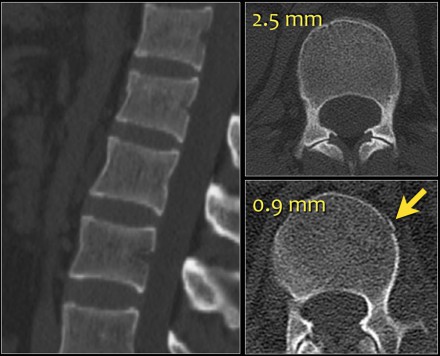

The images show a compression fracture.

All we see is a cortical disruption in the upper anterior wall of the vertebral body and slight loss of height ventrally.

The posterior vertebral cortex is intact.

The sagittal reformatted image also shows the cortical disruption.

Notice that on a 2.5mm axial slice you can miss these fractures.

You have to look at the thin slices to detect such a subtle fracture.